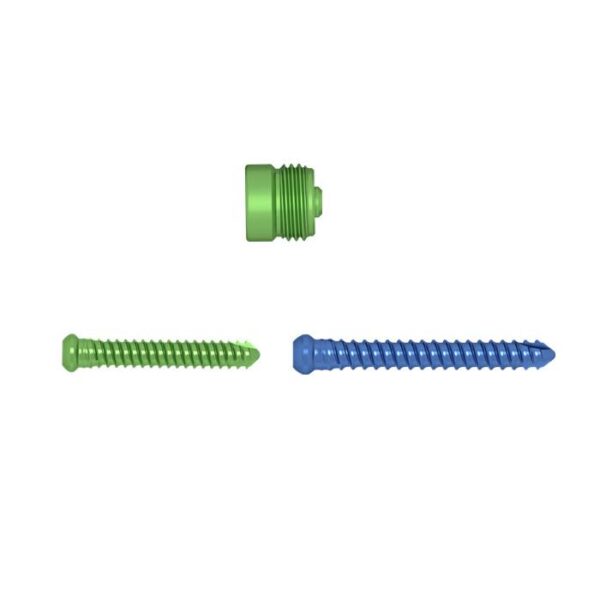

Empulgueras:

- Tornillo de bloqueo de 5,0 mm

- Tornillo de bloqueo de 6,0 mm

- Tapa final

Tornillos de bloqueo:

- Diseño de ranura autorroscante para facilitar la inserción.

- Rebajo Torxdrive del diseño de la cabeza del tornillo para reducir el tornillo suelto.

- Agujeros proximales dinámicos y estáticos con tornillo de bloqueo de 5.0 mm.

- Tres orificios transversales distales coinciden con el tornillo de bloqueo de 6,0 mm.

Tapa final:

- Evita que los tejidos blandos crezcan.